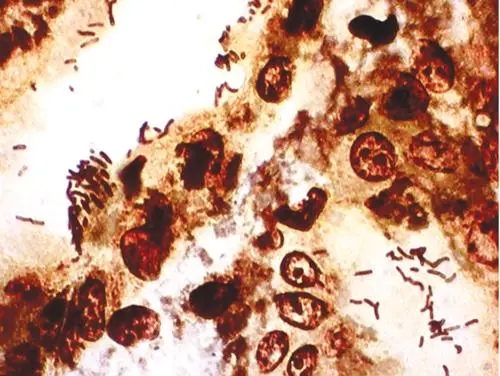

番紅o染色

番紅o染色:番紅(也稱作番紅O或基本紅2)是個(gè)用在組織學(xué)和細(xì)胞學(xué)的生物染色劑。番紅在一些染色的實(shí)驗(yàn)計(jì)劃表中用作復(fù)染劑,將所有的細(xì)胞核染成紅色。這在革蘭氏染色和內(nèi)孢子染色都是典型的復(fù)染劑。它也可以被用

番紅o染色:番紅(也稱作番紅O或基本紅2)是個(gè)用在組織學(xué)和細(xì)胞學(xué)的生物染色劑。番紅在一些染色的實(shí)驗(yàn)計(jì)劃表中用作復(fù)染劑,將所有的細(xì)胞核染成紅色。這在革蘭氏染色和內(nèi)孢子染色都是典型的復(fù)染劑。它也可以被用來(lái)檢測(cè)軟骨、黏蛋白和肥大細(xì)胞的顆粒。